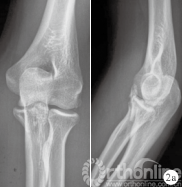

图 2 患者,男,23 岁,左侧尺骨冠状突骨折(Ⅱ型)

a.术前肘关节正侧位 X 线片